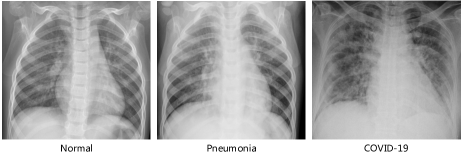

Accordingly, deep learning based methods for detecting COVID-19 with chest X-ray (CXR) have been developed and shown to be able to achieve accurate and speedy detection [12, 13]. For instance, a tailored convolution neural network platform trained on open source dataset called COVIDNet in [14] was proposed for the detection of COVID-19 cases from CXR. Oh et al. [15] proposed a novel probabilistic gradient-weighted class activation map to enable infection segmentation and detection of COVID-19 on CXR images. Fig. 1 shows three samples from the COVIDx dataset [14] which contains three different classes: normal, pneumonia and COVID-19. However, due to the similar pathological information between pneumonia and COVID-19 in the early stage, the CXR samples may have latent features distributed near the category boundaries, which can be easily misclassified by the hyper-plane learned from the limited training data. Moreover, to the best of our knowledge, most of the existing methods for COVID-19 detection are designed to extract the lower-dimension latent representations which may not be able to fully capture statistical characteristic of complex distributions (i.e., non-Gaussian distribution). Furthermore, quantifying uncertainty in COVID-19 detection is still a major yet challenging task for doctors, especially with the presence of noise in the training samples (i.e., label noise and image noise).

We use a public chest X-ray dataset, referred to as COVIDx, to evaluate the proposed model, which is published by the authors of COVID-Net [14]. This dataset contains a total of 13975 CXR images from 13870 patients of 3 classes: (a) normal (no infections); (b) pneumonia (non-COVID-19 pneumonia); (c) COVID-19. It contains samples from five open source available data repositories https://github.com/lindawangg/COVID-Net/blob/master/docs/COVIDx.md. Three random CXR samples of these three classes are shown in Fig. 1. To reduce the negative effect caused by extremely unbalanced training samples, i.e., very limited number of COVID-19 positive cases compared to the other two categories, we further include other open-source CXR datasets from https://www.kaggle.com/c/rsna-pneumonia-detection-challenge/data. Following [14, 47], the dataset is finally divided into 13624 training and 1510 test samples. The numbers of samples from different categories used for training and testing are summarized in Table I. Moreover, we also adopted various data augmentation techniques to generate more COVID-19 training samples, such as flipping, translation, rotation using random five different angles, to tackle the data imbalance issue such that the proposed model can learn an effective mechanism of detecting COVID-19.